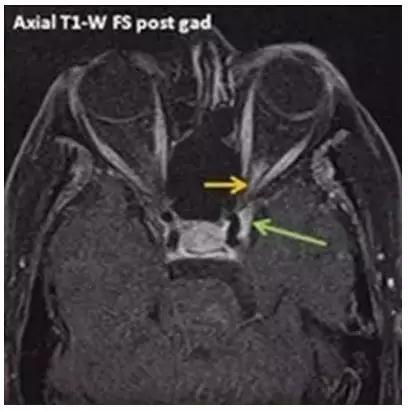

9點(diǎn)后,病房陸續(xù)迎來了4位新住院患者,其中一位是免疫性眼病患者,來自安徽,凌晨5點(diǎn)就從家出發(fā)來我們新院了,她頭痛劇烈,受累眼睛視力幾近失明,行走都需要她女兒攙扶,她是專門奔我們科而來,她的病名叫“Tolosa Hunt綜合征”,該病是罕見病中的罕見病,發(fā)病率只有1/100萬,該病診治困難,個體化治療非常重要。免疫性眼病是我們科的診療特色,診療經(jīng)驗(yàn)較為豐富,僅通過一天的治療,患者癥狀明顯改善。